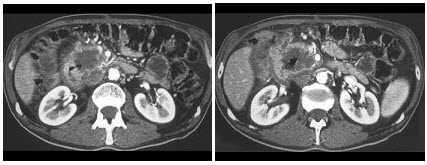

16、多项选择题

男,65岁,左腰部隐痛不适2月,CT平扫+增强如图所示,下列说法正确的是()

A.平扫时可见左肾局部隆起,腹主动脉旁、肾门部有等密度的块影

B.增强扫描可见左肾局部隆起病灶有不均匀强化

C.腹主动脉旁、肾门部的块影与左肾内的病灶强化方式相同

D.腹腔内未见积液,所示骨质亦未见破坏

E.考虑为左肾癌伴肾门淋巴结转移